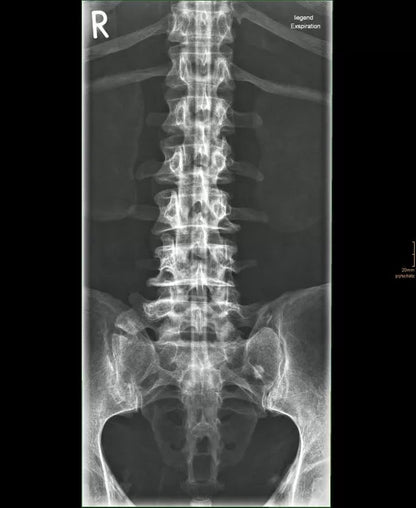

The whole-body X-ray phantom serves for practical training in projection radiography as well as in positioning and positioning techniques. It enables the production of realistic X-ray images under training conditions and depicts anatomical structures in their natural size.

The phantom contains a natural human skeleton. Additionally, the outlines of the larynx, lungs, heart, and kidneys are integrated, appearing as shadows on the X-ray images. This allows for the creation of images that accurately reflect the conditions found in patients. The use of a real skeleton enables the identification of bony landmarks that are not visible in plastic models.

The joints are mounted with full mobility, allowing positioning in common radiological standard positions, including special positions such as the frog position and pronation and supination of the forearm. The arms can be raised, so the phantom can also be used for bone examinations in CT scans. Particular attention was paid during assembly to the realistic representation of the joint spaces.

Each phantom is a handcrafted, unique piece. Variations in size, design, and appearance are possible. Depending on the model, pathological findings may be present. The revised design was developed in collaboration with a German training institution for medical-technical radiology assistants and meets the requirements of modern training concepts.